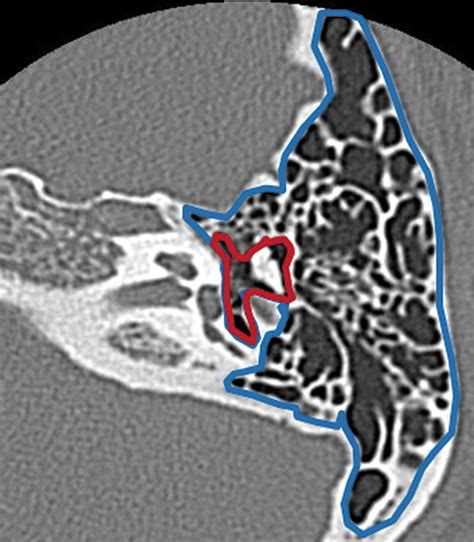

Because the mastoid air cells are deeply embedded within the skull, they cannot be seen through a standard physical ear examination. Instead, doctors rely on advanced imaging techniques to assess their health and structure. These imaging tools are essential for diagnosing conditions like chronic ear infections, mastoiditis, or detecting anatomical abnormalities.

Computed Tomography (CT) Scan The gold standard for visualizing the bony structure and identifying fluid or infection in the air cells.